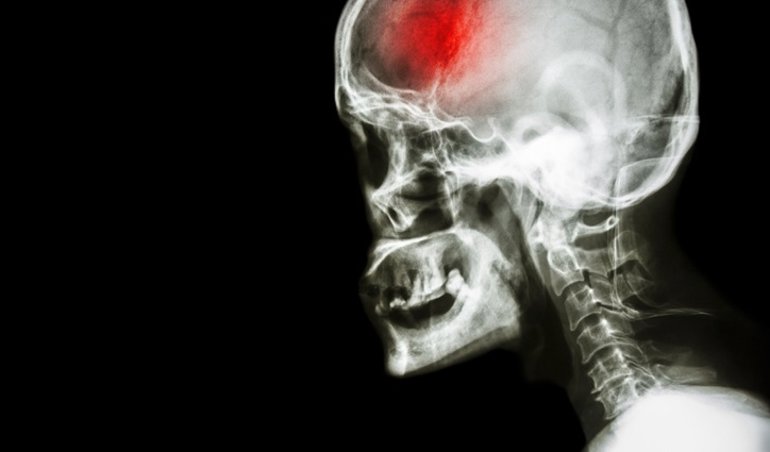

La trombectomía es una opción segura equiparable al tratamiento farmacológico para el ictus Un procedimiento quirúrgico denominado trombectomía es una opción de tratamiento segura y viable para un tipo poco frecuente de ictus, según un estudio publicado en 'Radiology', revista de la Sociedad Radiológica de Norteamérica (RSNA).